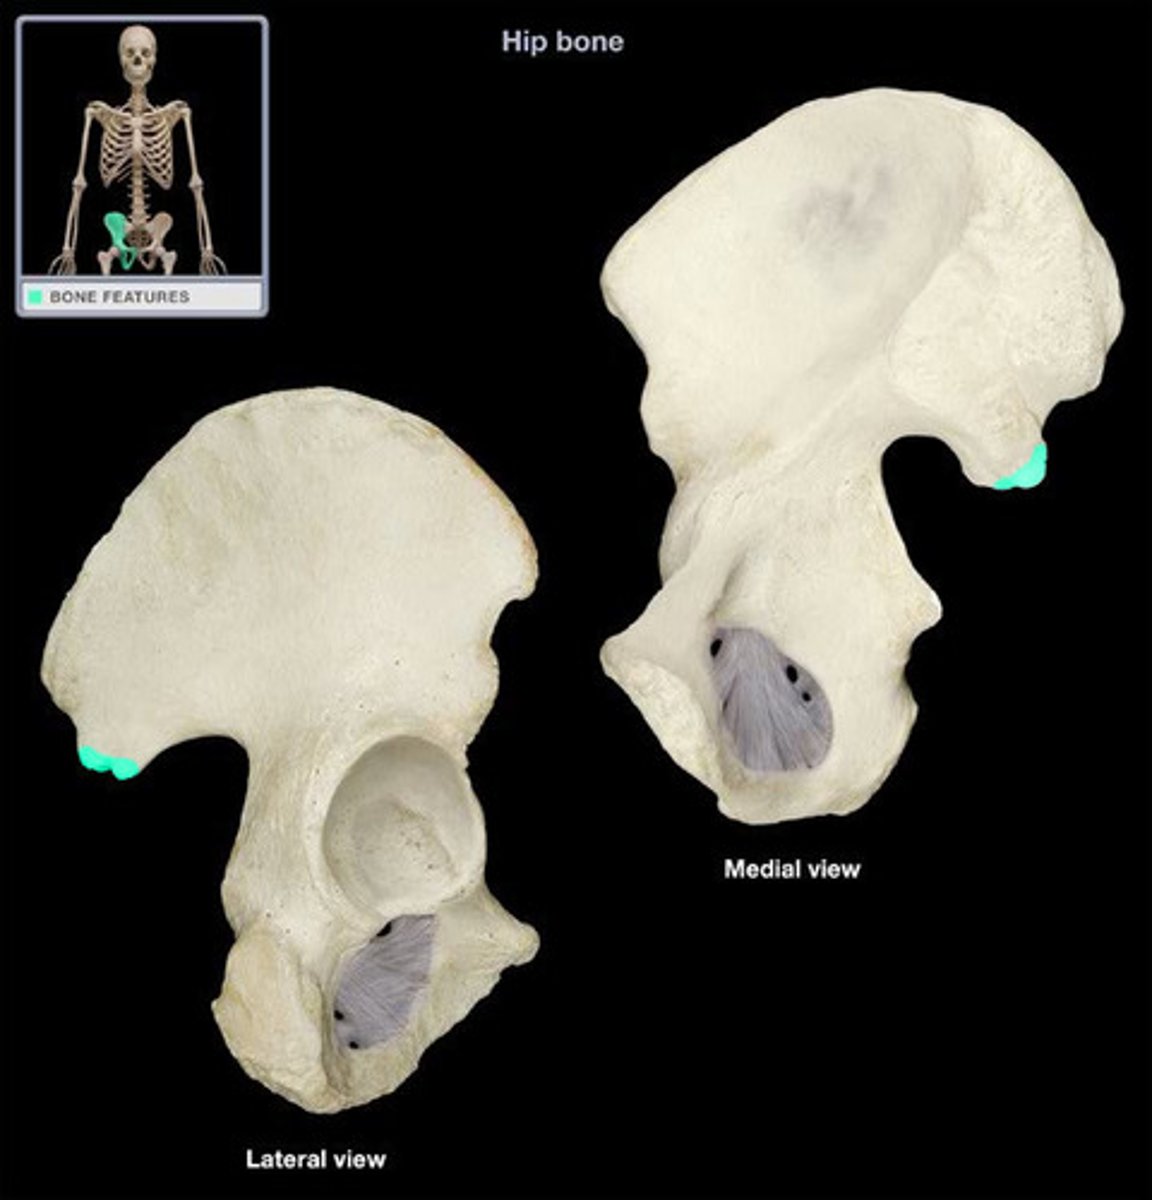

ox coxae

hip bones

3 bones fused together, anteriorly connected at the pubic symphysis and posteriorly at the sacrum

ilium

weight bearing during sitting

pubis

The medial anterior portion of the pelvis

ischium

the lower, posterior portions of the pelvis

iliac crest

upper margin of iliac bones

posterior superior iliac spine

the sharp posterior end of the iliac crest

posterior inferior iliac spine (PIIS)

a bony projection located inferior to the posterior superior iliac spine

anterior superior iliac spine

origin of sartorius

anterior inferior iliac spine (AIIS)

origin of rectus femoris

iliac fossa

The broad, slightly concave inner surface of the ilium.

Acetabulum

large socket in the pelvic bone for the head of the femur

acetabular notch

deep notch in the inferior part of the brim

greater sciatic notch

allows blood vessels and the large sciatic nerve to pass from the pelvis posteriorly into the thigh

ischial tuberosity

receives the weight of the body when sitting

body of ischium

Makes up all of the ischium superior to the tuberosity

ramus of ischium

joins the inferior ramus of the pubis anteriorly

obturator foramen

opening in hip bone formed by the pubic and ischial rami

body of pubis

origin of adductor longus

arcuate line

a ridge of bone that runs inferiorly and anteriorly from the auricular surface, forms pelvic brim

iliopubic eminence

marks the point of union of the ilium and the pubis just lateral to the arcuate line

pubic tubercle

An attachment point for the inguinal ligament.

superior ramus of pubis

origin of pectineus

inferior ramus of pubis

origin of adductor brevis